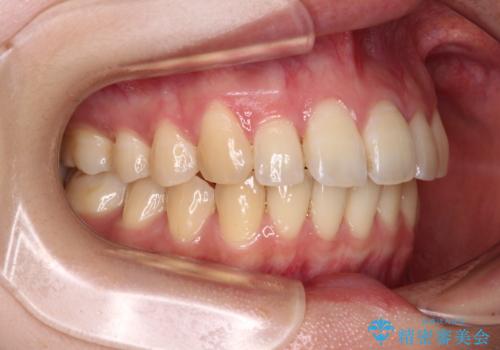

- 前歯の突出感を気にして来院された患者様です。

左右ともに奥歯の咬み合わせが上顎前突となっており、上顎前歯が飛び出している状態でした。

奥歯の咬み合わせ改善が必要であるため、マウスピース矯正より確実に達成のできるワイヤー矯正にて治療を行うこととしました。

奥歯の咬み合わせはしっかりと改善され、前歯の突出感も改善されました。